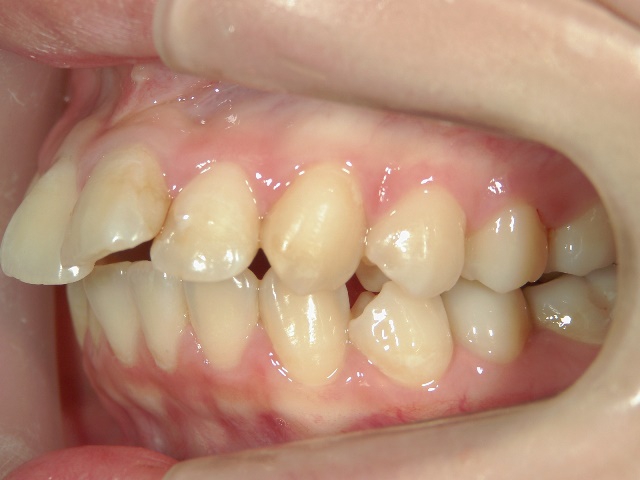

no.6_8296_治療前_右.jpgno.6_8296_治療前_正面.jpgno.6_8296_治療前_左.jpg